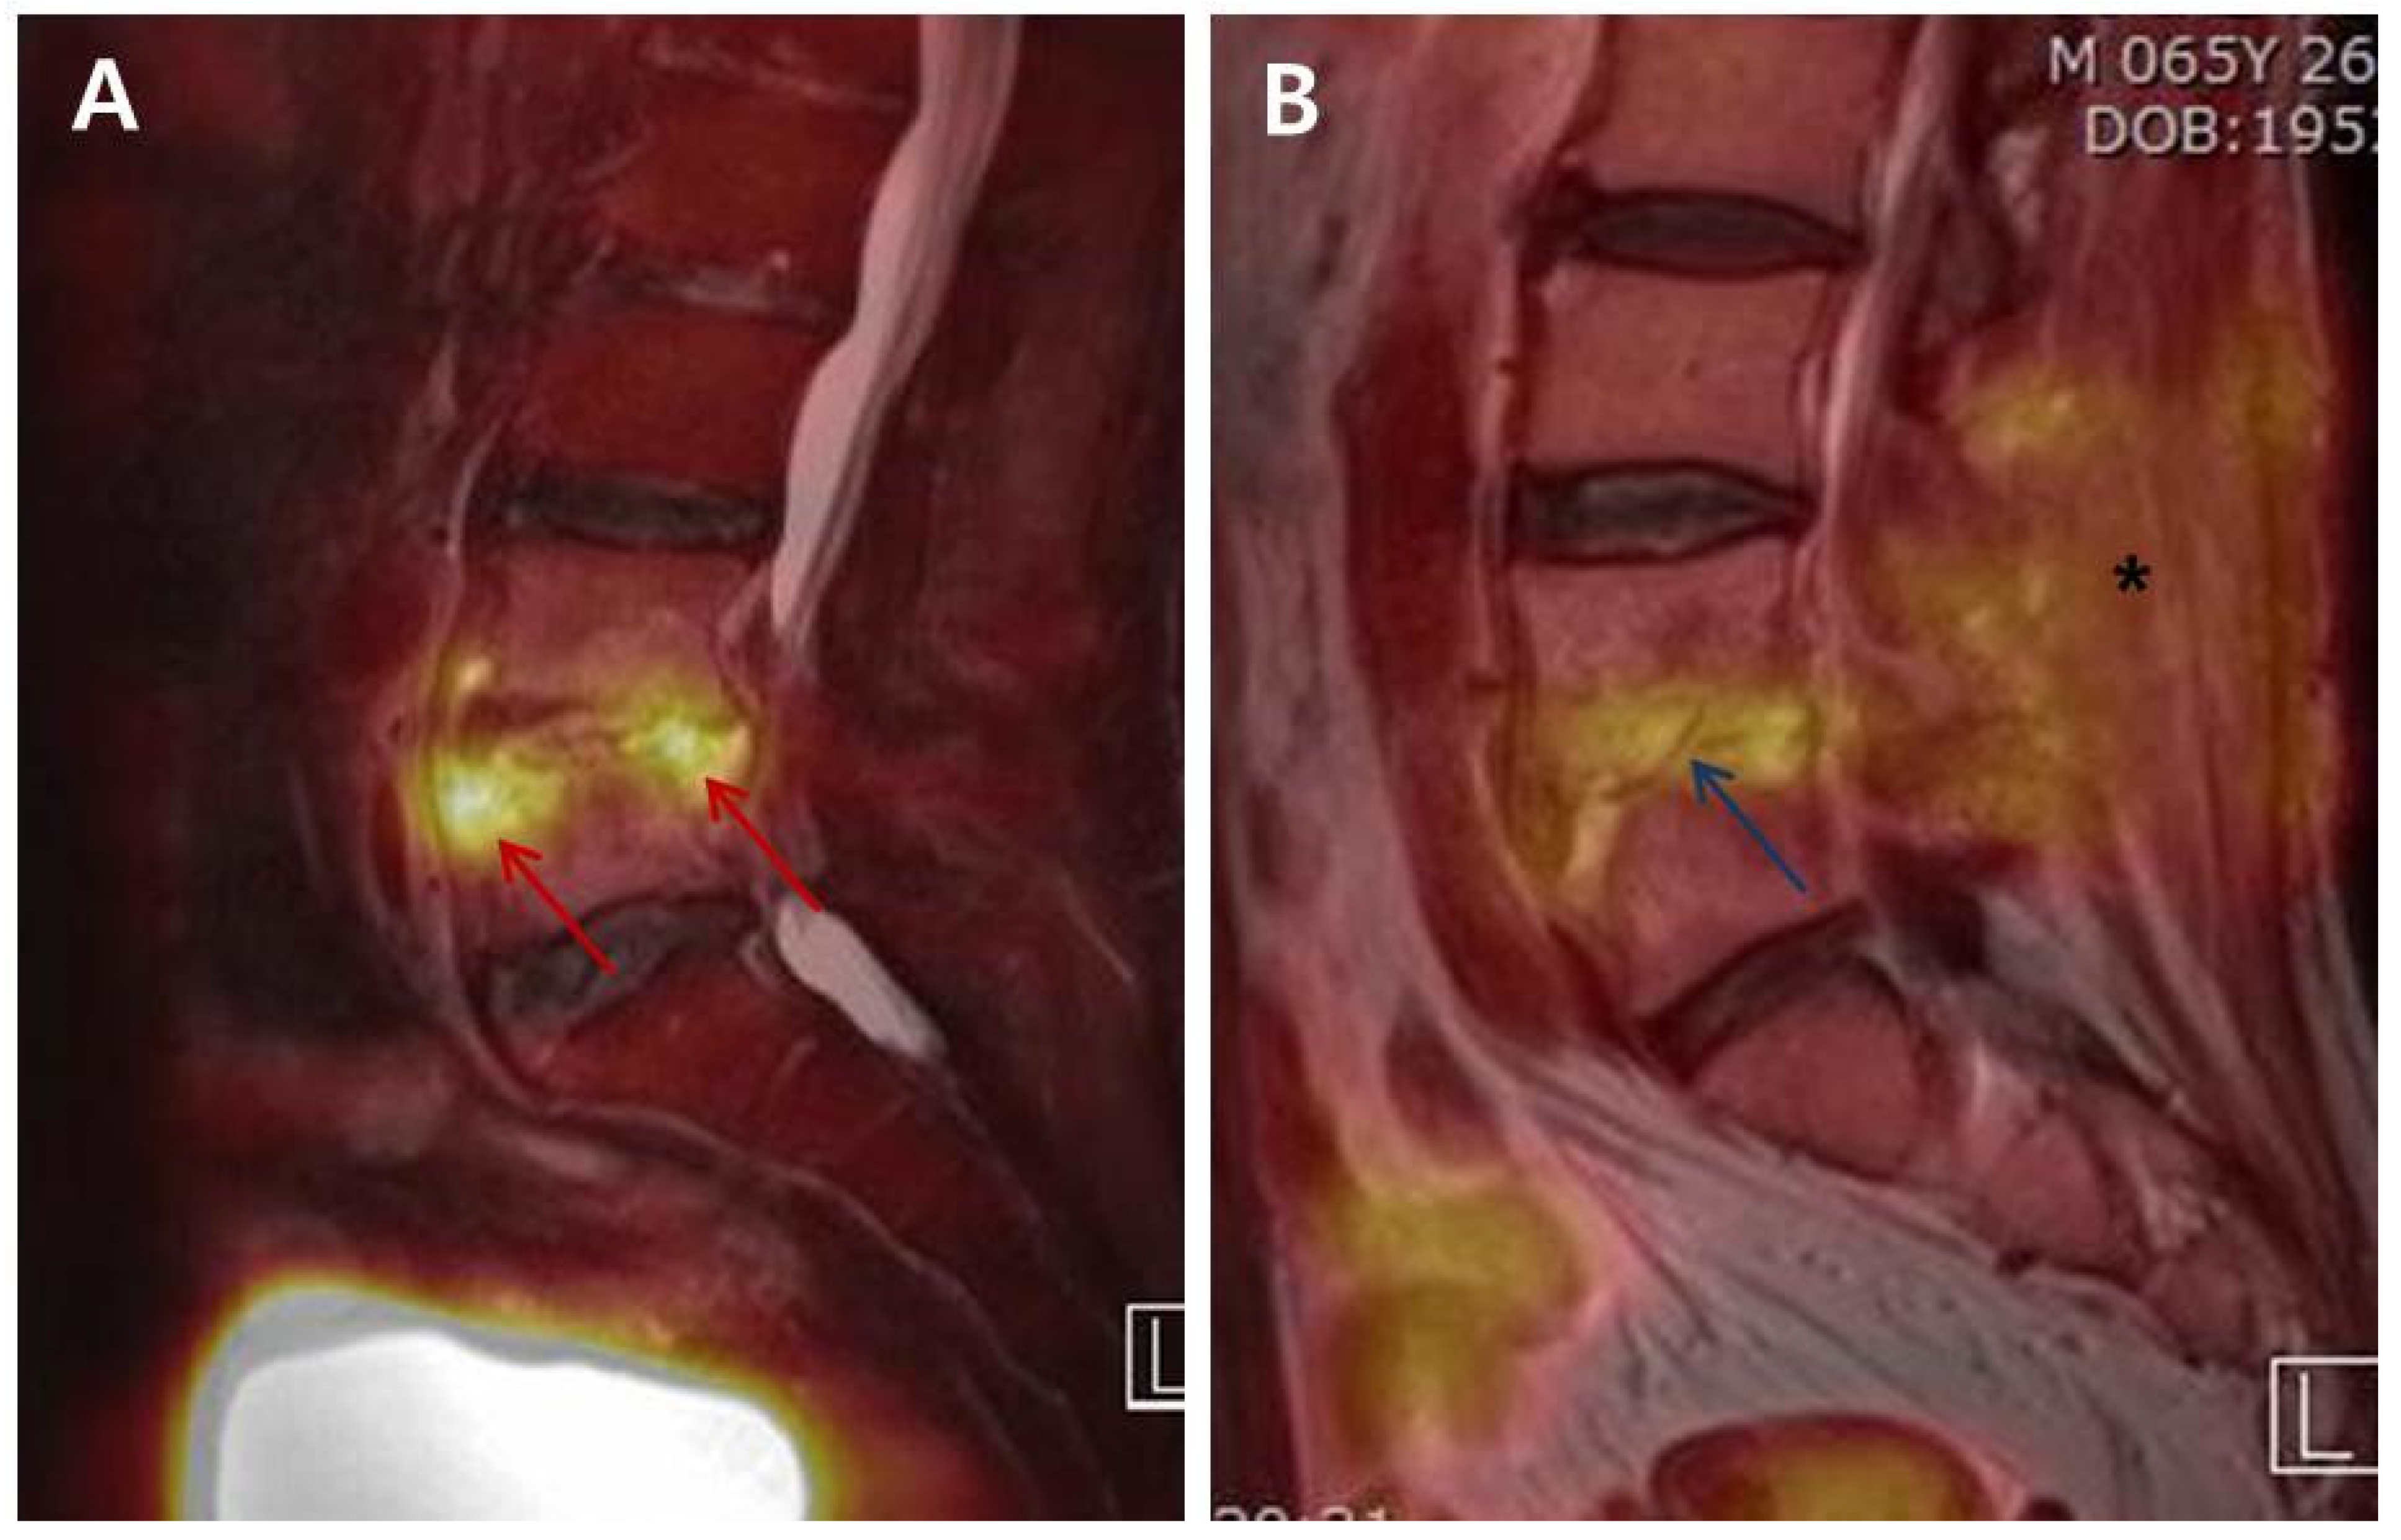

Jeon et al. [,] investigated the change of FDG uptake according to the phases of osteomyelitis based on the pathophysiological features of osteomyelitis. The early phase of PVO is characterized by activated neutrophil accumulation, known as the respiratory burst, which uses greater amounts of glucose as the main energy source for chemotaxis and phagocytosis []. In the chronic phase, lymphocytes are the most predominant cell type, followed by plasma cells, histiocytes, and some polymorphonuclear leucocytes []. The transport of FDG across the cellular membrane is mediated by the glucose transporter of cell membrane, which is more abundantly found on the activated inflammatory cells []. Consequently, FDG uptake increases by the activated granulocytes in the acute phase. On the other hand, in the chronic or recovery phase, lymphocytes are the predominant inflammatory cells. In addition, there are formations of fibroses around the foci of inflammation and bone marrow, fatty changes, increased osteoblasts facilitating new bone formation, and dilated blood vessels []. The mechanical stress on the intervertebral disc and endplates depends on the patient’s activities in addition to the formation of fibrosis and granulation tissues during the recovery phase []; these can result in the sustained increase of FDG uptake at the intervertebral disc and endplates even after successful treatment compared to widely FDG uptake on uncontrolled cases (Figure 3).

Figure 3.

Differences in the intensity of FDG uptake between Uncontrolled (group UC) and Controlled (group C) simultaneous 18F-FDG-PET/MRIs. (A) The 60-year-old male patient diagnosed as PVO on L4–L5 was treated with empirical vancomycin and ciprobay under the no causative bacterial identification. The clinical assessment on the 36th day of parenteral antibiotic therapy showed sustained back pain, intermittent mild fever, and ESR/CRP of 57/7.726. 18F-FDG-PET/MRI of group UC revealed an increased FDG uptake (red arrow; SUVmax 9.26) on the anterior and posterior corners of upper L5 body and the disc of L4-L5. (B) The 65-year-old male patient diagnosed as postoperative PVO on L4–L5 was treated with nafcillin under the identification of MSSA. The patient showed alleviation in back pain, no fever, and ESR/CRP of 30/0.09 in the clinical assessment on the 35th day. The FDG uptake decreased overall and was limited to the disc and endplates (blue arrow; SUVmax 3.82) on 18F-FDG-PET/MRI of group C. There was also decrease in FDG uptake at posterior structures, including back muscle and fatty layer (asterisk). FDG, 18F-fluorodeoxyglucose; PVO, pyogenic vertebral osteomyelitis; MSSA, methicillin-sensitive Staphylococcus aureus; ESR, erythrocyte sedimentation rate (mm/h); CRP, C-reactive protein (mg/dL); 18F-FDG-PET/MRI, 18F-fluorodeoxyglucose positron emission tomography/magnetic resonance imaging; SUVmax, maximum standardized uptake value of FDG.